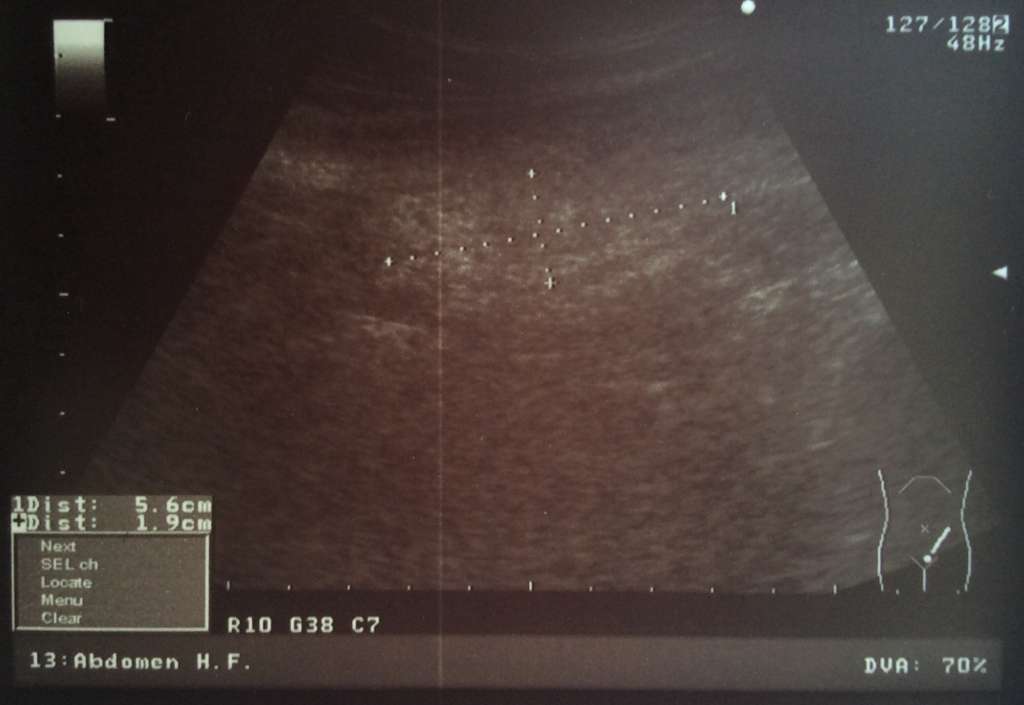

УЗИ Рак сигмовидной кишки фото